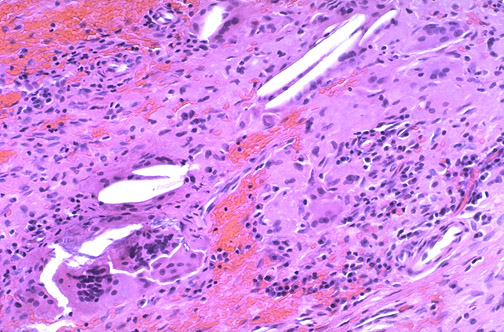

Surrounding the cyst is an inflammatory reaction with

foreign body giant cells

and mononuclear cells. Hemorrhage and necrosis leads to formation of

cholesterol clefts

.